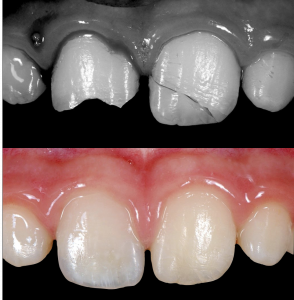

M. S., 10 anni. Un martedì mattina, a scuola durante la ricreazione, cade mentre scende le scale: sbatte mento e bocca sullo spigolo di un gradino procurandosi, oltre ad una brutta lacerazione del labbro, la frattura della corona dei due incisivi superiori. Il frammento dell’incisivo superiore sinistro viene ritrovato e conservato nel latte.

Dopo un paio d’ore al pronto soccorso, nel primo pomeriggio giunge presso il mio studio. Fortunatamente le linee di frattura non hanno coinvolto il nervo ed entrambe gli elementi risultano essere ancora vitali. Dopo aver suturato la brutta lacerazione al labbro, decido di utilizzare due approcci diversi per riabilitare i due denti: ho ricostruito manualmente il centrale di destra (a sinistra nella foto) e di incollare il frammento ritrovato al centrale di sinistra (a destra nella foto). Ho rivisto M.S. dopo 7, 15 e 30 giorni, poi di nuovo a 3, 6 e 12 mesi dall’incidente. I denti sono sempre rimasti vitali, non si sono decolorati e l’estetica è stata mantenuta; questo è successo grazie allla prontezza nel recuperare almeno un frammento che ha permesso di ricreare le geometrie originali, di conservarlo nel modo opportuno e di giungere all’attenzione di un odontoiatra nel più breve tempo possibile.